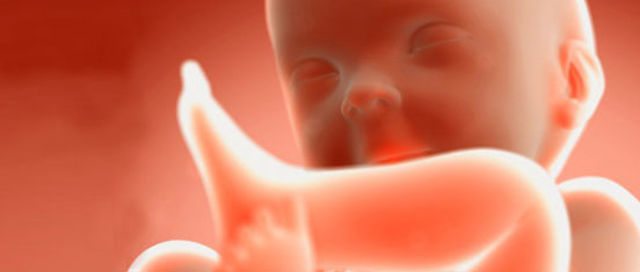

En los rasgos externos la cabeza está erecta, el cuello está casi recto y bien definido, también el oído externo adopta su forma y se ha desplazado casi a su posición definitiva en la cabeza

• Period: to

12 SDG

El saco vitelino se ha retraído, el feto deglute líquido amniótico y puede responder a la estimulación de la piel, los ovarios descienden por debajo del reborde pélvico, también se produce la hormona paratiroidea y la sangre se puede coagular